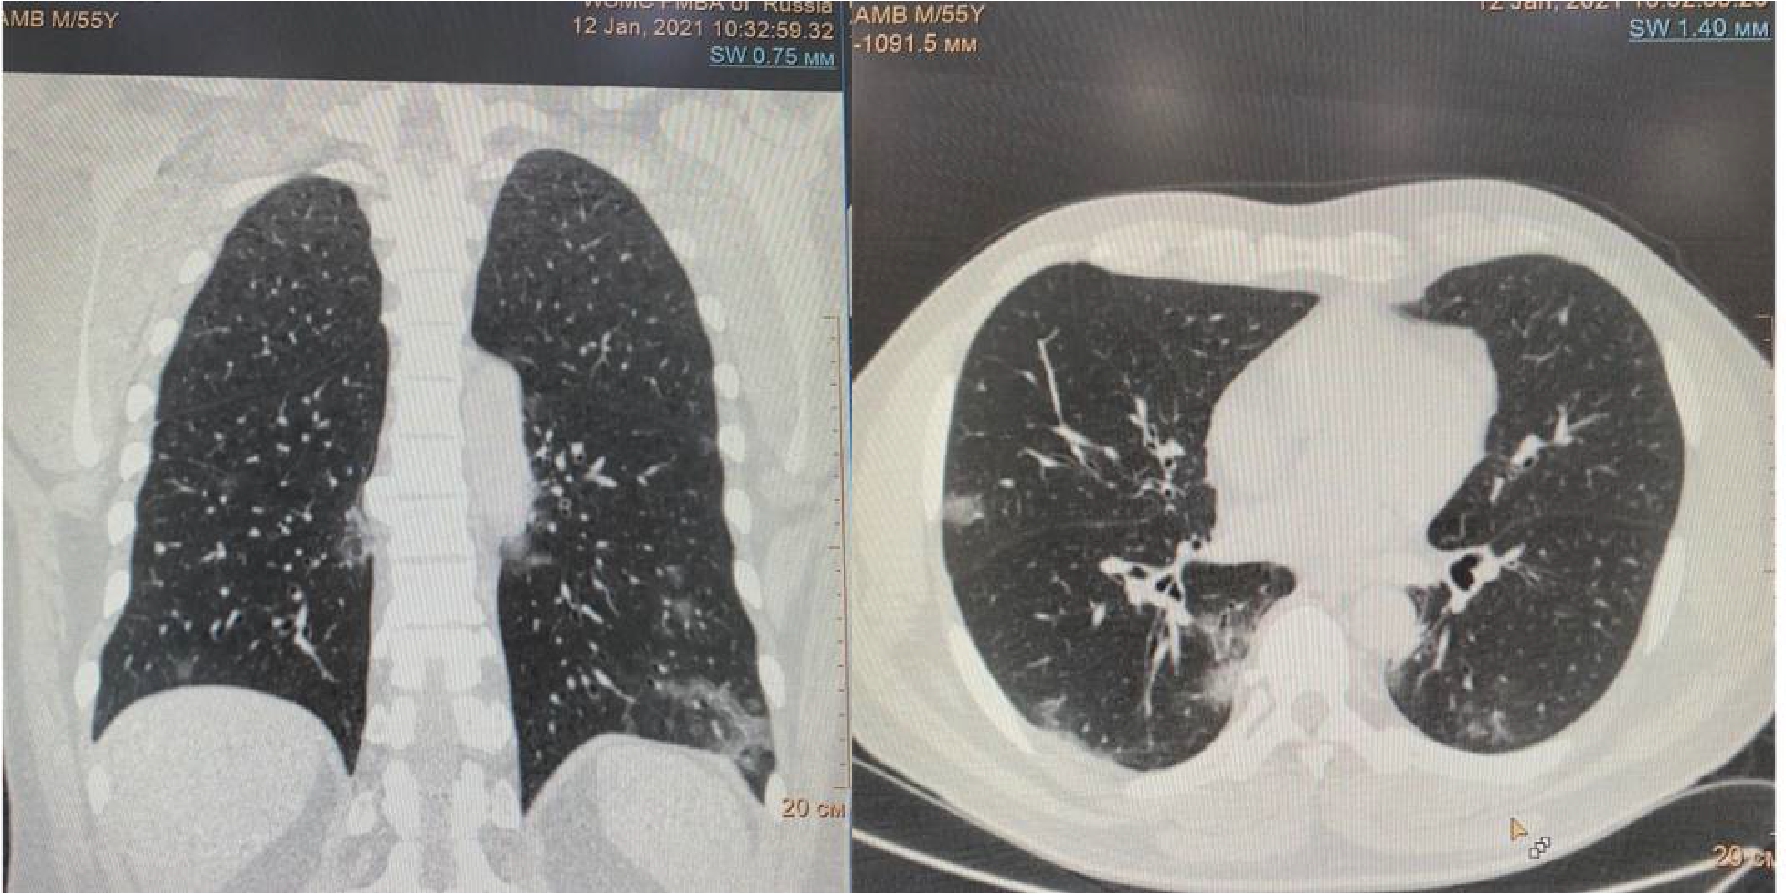

Рисунок 2. МСКТ органов грудной клетки – признаки двусторонней полисегментарной интерстициальной пневмонии (объем поражения 40%, КТ-2)

На 4-е сутки госпитализации выявлено ухудшение клинического статуса (снижение SpO2 до 93%, температура тела более 38 0С), отрицательная динамика по МСКТ (объем поражения 28%, КТ-2, в связи с чем к лечению добавлен олокизумаб однократно, без отчетливого клинического эффекта. На 7-е сутки госпитализации МСКТ выявила дальнейшее прогрессирование поражения легких (объем поражения 40%, КТ-2 (рис.2) на фоне сохранения умеренно выраженного кашля (со скудной мокротой), нарастания дыхательной недостаточности (SpO2 85-88% без инсуффляции кислорода). Больной переведен в отделение анестезиологии и реанимации, где находился в течение 3 суток, лечение включало преднизолон 480 мг/сут (начальная доза), противокашлевый препарат центрального действия (бутамират), проведен плазмоферез (аппарат Fenwal; инфузия плазмы - 2440 мл, эксфузия плазмы - 1430 мл) с введением антиковидной плазмы (270 мл).

В связи со стабилизацией состояния на 3-е сутки проводимой терапии пациент переведен в отделение для лечения пациентов с COVID-19, не нуждающихся в проведении ИВЛ. Следует отметить, что кашель был купирован, сохранялись жалобы на одышку, общую слабость.